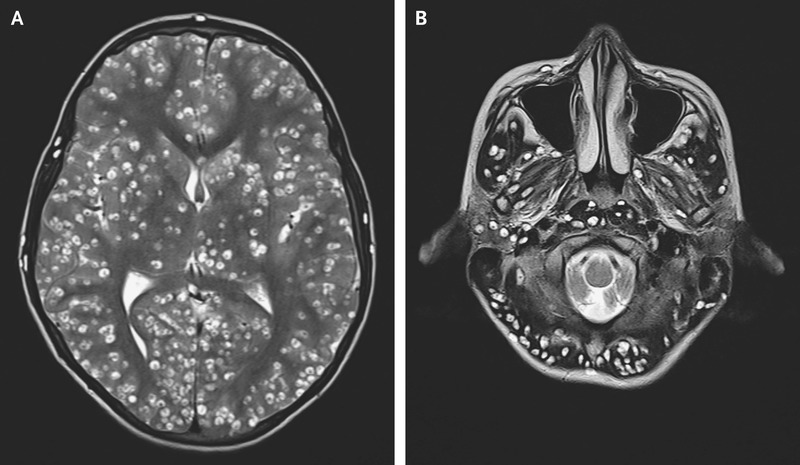

Afin de comprendre la pathologie du patient, les médecins ont décidé d’observer le cerveau du jeune homme à l’aide d’une IRM. Celle-ci a mis en évidence de nombreuses lésions kystiques bien définies dans tout le cortex cérébral (photo de gauche), le tronc cérébral et le cervelet (photo de droite). Ces lésions sont compatibles avec une pathologie appelée la neurocysticercose.